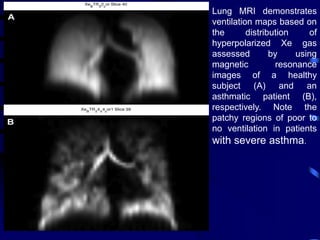

Lung MRI demonstrates

ventilation maps based on

the distribution of

hyperpolarized Xe gas

assessed by using

magnetic resonance

images of a healthy

subject (A) and an

asthmatic patient (B),

respectively. Note the

patchy regions of poor to

no ventilation in patients

with severe asthma.

Lung MRI demonstrates ventilationmaps based on the distribution of hyperpolarized Xe gas assessed by using magnetic resonance images of a healthy subject (A) and an asthmatic patient (B), respectively. Note the patchy regions of poor to no ventilation in patients with severe asthma.